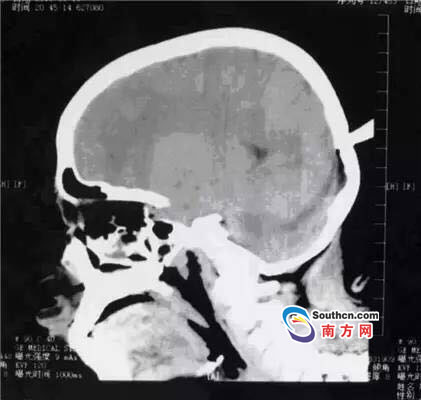

接到小玲受傷的消息,東莞市第三人民醫(yī)院急診科立即啟動了急癥危重患者搶救流程。急癥頭部CT顯示,飛鏢已穿透小玲的顱骨,并突破硬腦膜,情況非常兇險,小玲命懸一線。

此時,小玲也處于極度恐懼和不安中。醫(yī)生表示,必須及時手術(shù)取出異物、止血并妥善處理顱內(nèi)相關(guān)損傷,否則飛鏢將進一步損傷腦組織,引起二次傷害,甚至可能引發(fā)顱內(nèi)大出血。搶救刻不容緩,醫(yī)院神經(jīng)外科醫(yī)師立即與麻醉手術(shù)科聯(lián)系,開通綠色通道準(zhǔn)備急診手術(shù)。

開顱還是不開顱?這是擺在神經(jīng)外科醫(yī)生面前最重要的問題。此時的檢查結(jié)果無法判斷有無血管和腦組織的損傷,開顱手術(shù)可以直接看到損傷的情況,及時進行處理,但是如果飛鏢沒有損傷大血管,開顱的話就會造成比較大的創(chuàng)傷;不開顱手術(shù),手術(shù)的全過程造成的損傷就會減少,但是如果有大血管的損傷,不開顱直接拔出飛鏢,就不能及時進行止血和清創(chuàng)。

兩種選擇都是機會與風(fēng)險并存的,最后神經(jīng)外科通過會診,在充分征求家屬意見的基礎(chǔ)上,決定進行不開顱手術(shù),同時,也充分考慮手術(shù)風(fēng)險,做好開顱手術(shù)的一切準(zhǔn)備。